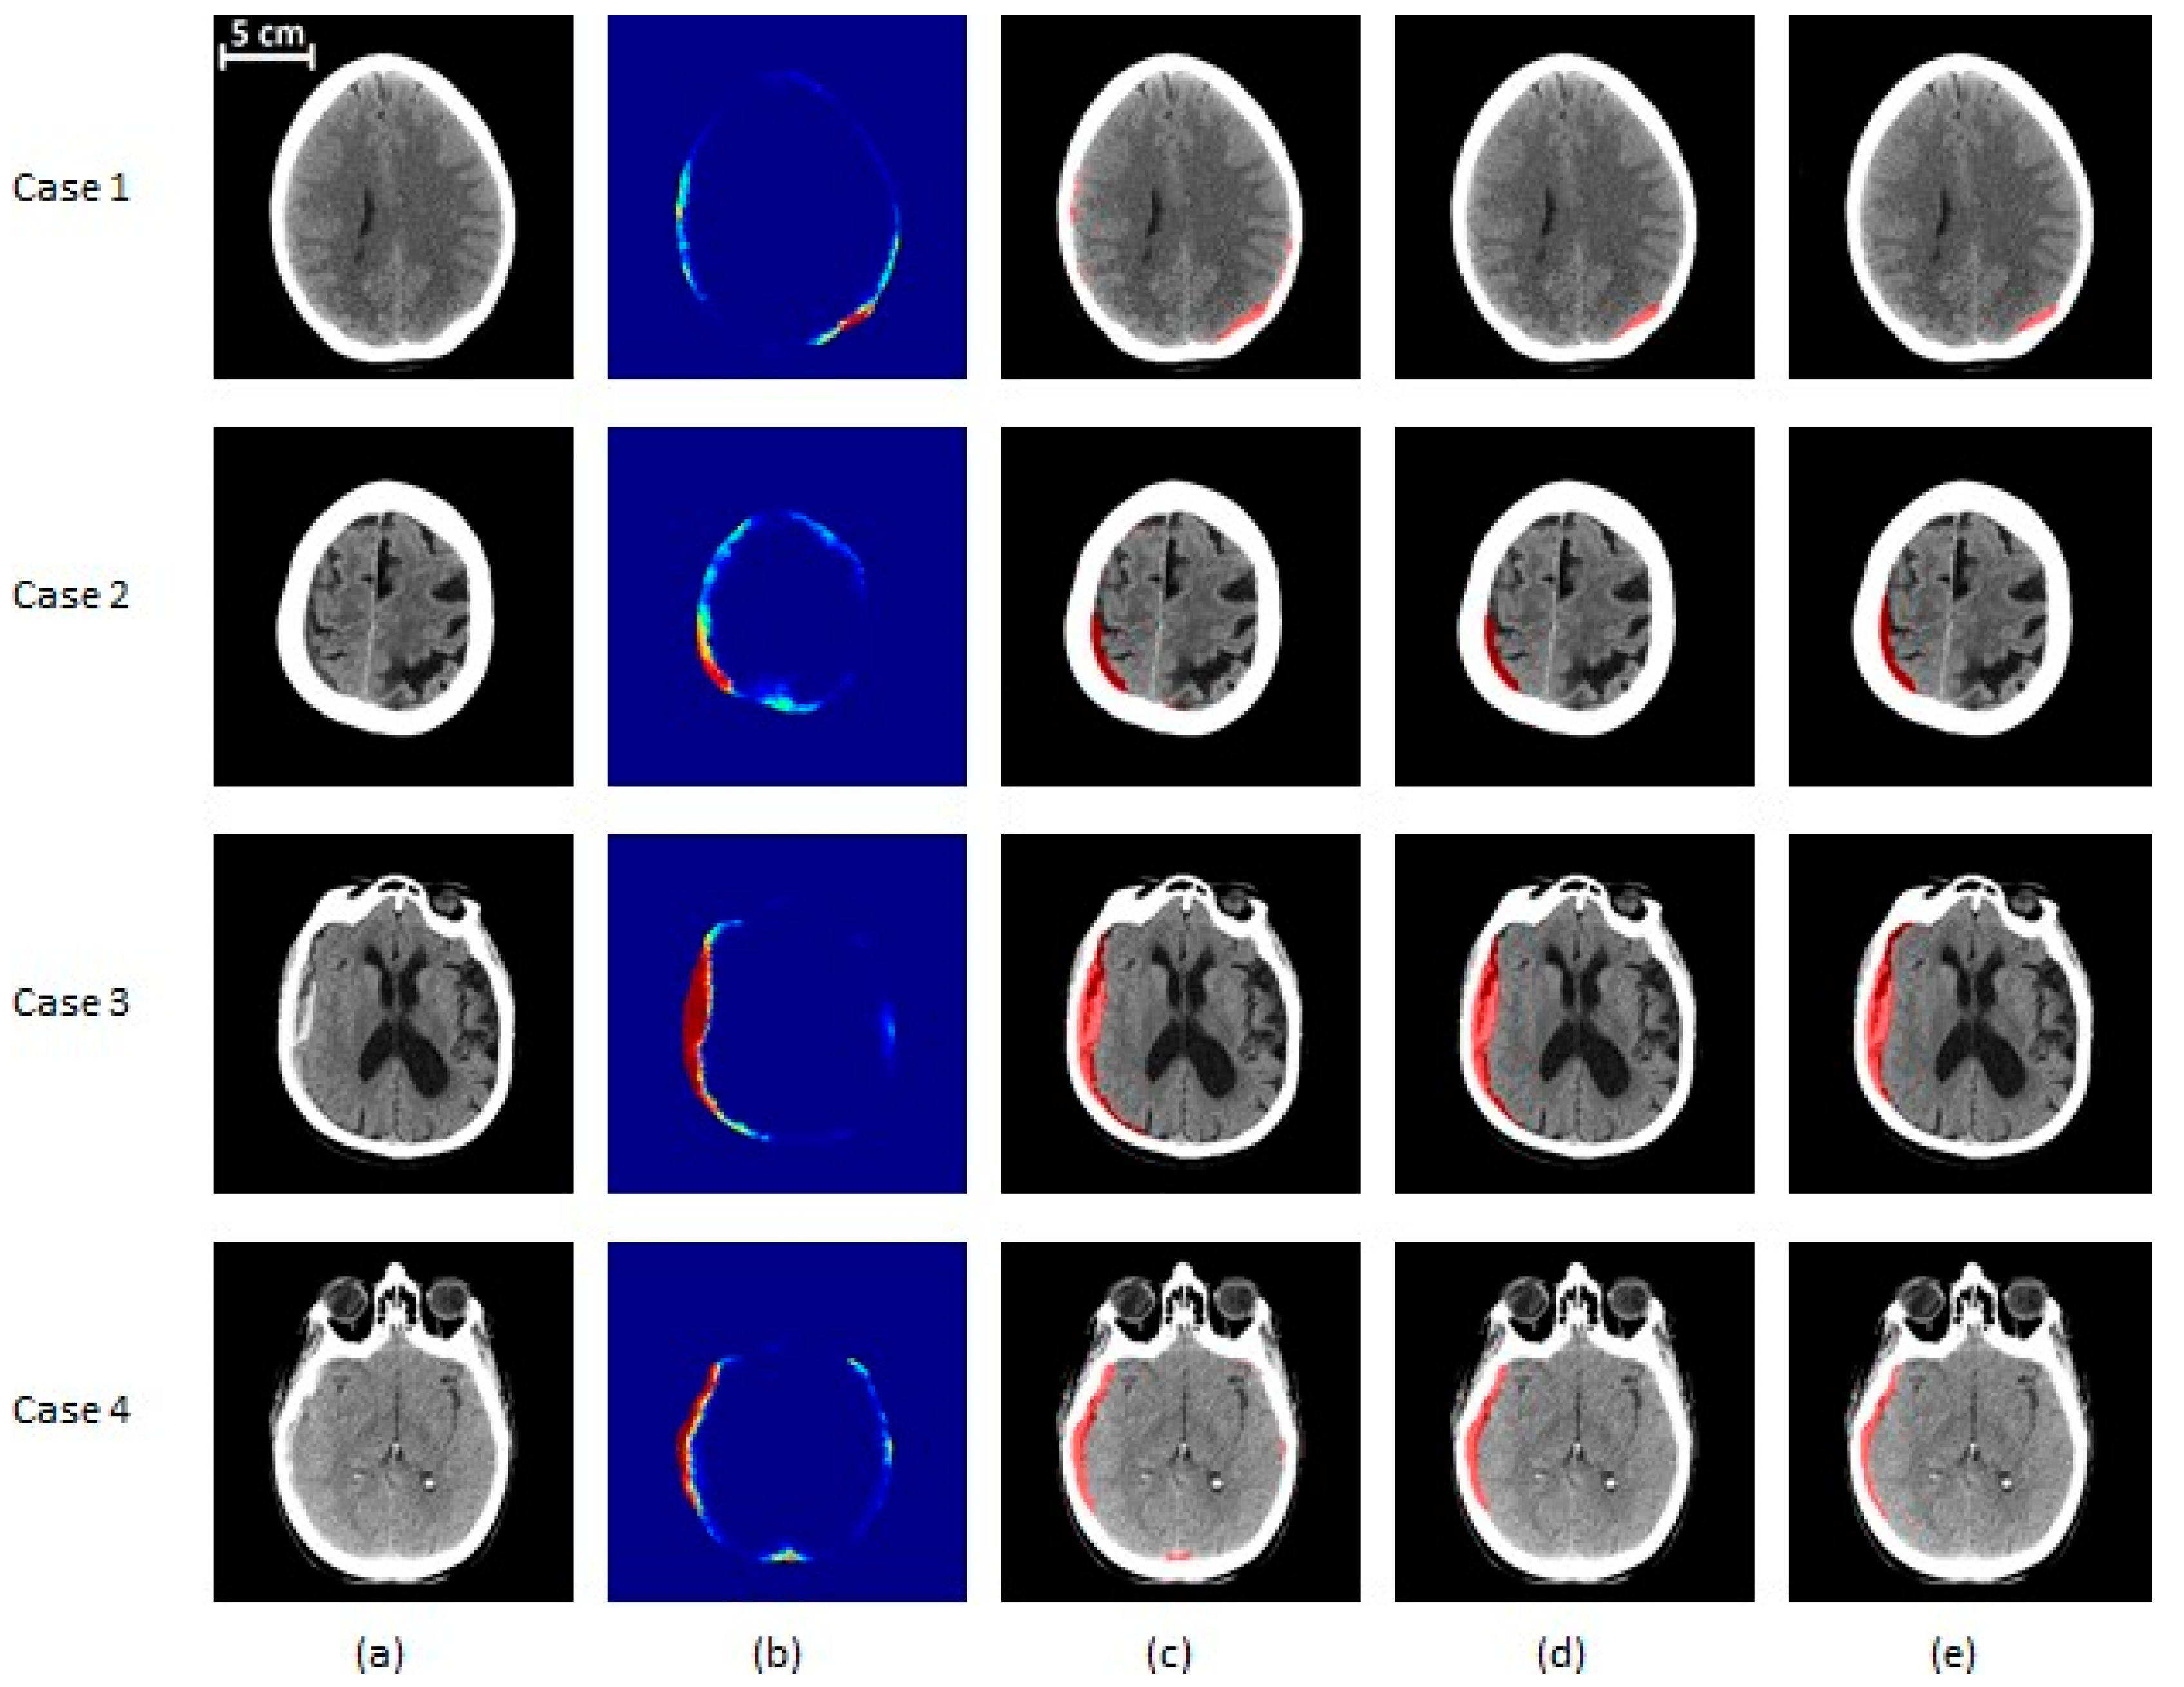

The results of the proposed segmentation algorithm at different stages are shown in

Figure 6 and

Figure 7. These images cover various combinations of size and type of subdural hematoma.

Figure 6.

SDH segmentation results on mild and moderate subjects. (a) The original CT image, (b) the probability map corresponding to the output of the classifier, (c) the segmented region before post-processing, (d) the segmentation result after post-processing, (e) the ground truth. Cases 1 and 2 are mild (<25 cc of blood) patients and cases 3 and 4 are moderate (25–50 cc of blood) ones. Cases 1, 3, and 4 are acute SDH, while case 2 is an example of a chronic hematoma. In (a,c–e), the gray region corresponds to brain texture in the original CT image. In (b), the colormap ranging from blue to red is associated with probability from zero to one.

Figure 6.

SDH segmentation results on mild and moderate subjects. (a) The original CT image, (b) the probability map corresponding to the output of the classifier, (c) the segmented region before post-processing, (d) the segmentation result after post-processing, (e) the ground truth. Cases 1 and 2 are mild (<25 cc of blood) patients and cases 3 and 4 are moderate (25–50 cc of blood) ones. Cases 1, 3, and 4 are acute SDH, while case 2 is an example of a chronic hematoma. In (a,c–e), the gray region corresponds to brain texture in the original CT image. In (b), the colormap ranging from blue to red is associated with probability from zero to one.